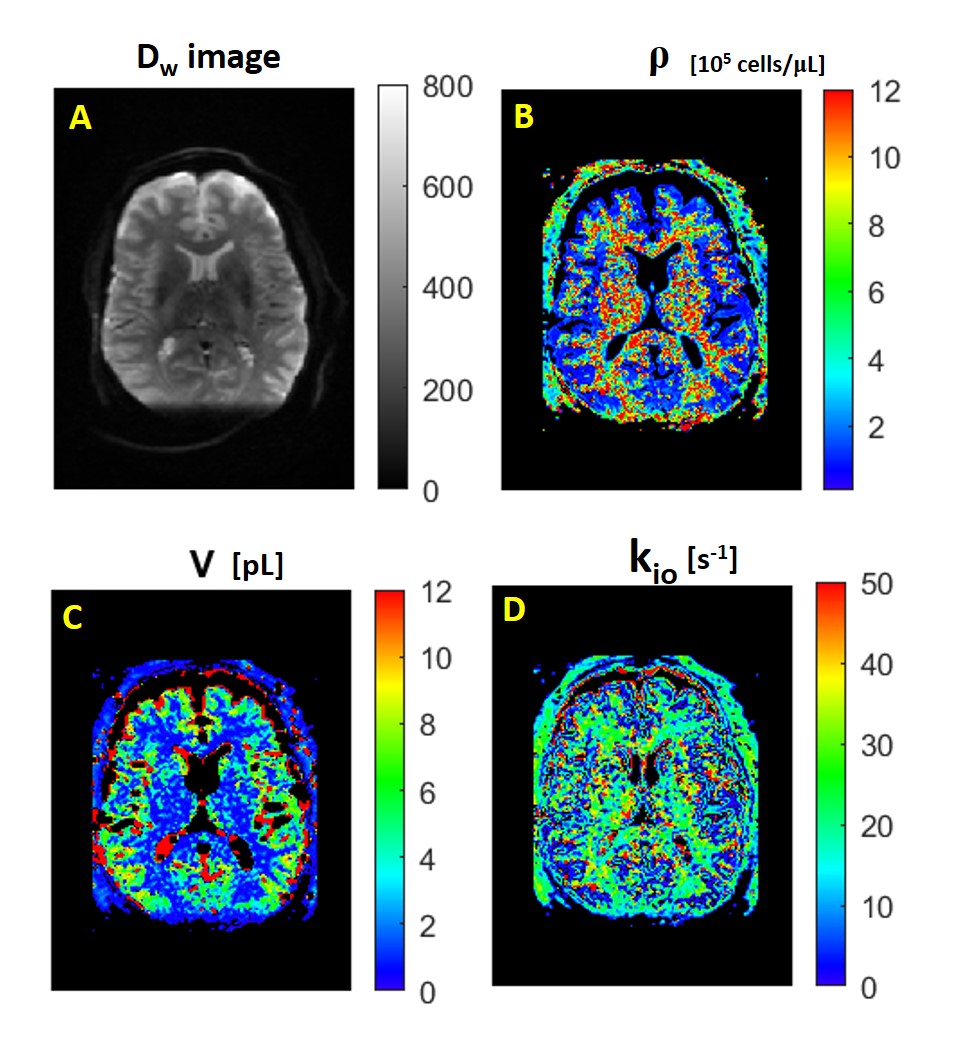

Figure 1A shows the axial DWI obtained at b = 335 s/(mm)2 in the third acquisition. Panels A-D show the MADI parametric maps: B) the voxel cell density (ρ, [105 cells/μL]) image; C) the voxel-mean cell volume (<V> [pL]) map; and D) the voxel-mean (<kio> [s-1]) image. These exhibit magnitudes and patterns consistent with the pathology and MADI literature: ρGM < ρWM; <V>GM > <V>WM, and <kio>GM < <kio>WM.2

Figure 1. Axial images from the third DWI acquisition. A) The Dw-image at b = 335 s/(mm)2. The MADI parametric maps: B) voxel cell density ρ [(105 cells)/μL], C) voxel-mean cell volume áVñ [pL], and D) voxel-mean homeostatic cellular water efflux rate constant ákioñ [s-1]. The patterns seen are as expected.